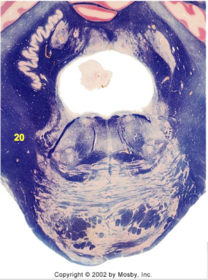

| Nucleus gracilis | |

| Accessory nucleus | |

| Medial longitudinal faciculus | |

| Pyramidal decussation | |

| Medullary pyramids | |

| Anterior spinocerebellar tract | |

| ALS | |

| Posterior spinocerebellar tract | |

| Spinal tract of V | |

| Spinal nucleus of V | |

| Nucleus cuneatus | |

| Fasciculus cuneatus | |

| Fasciculus gracilis | |

| Central canal | |